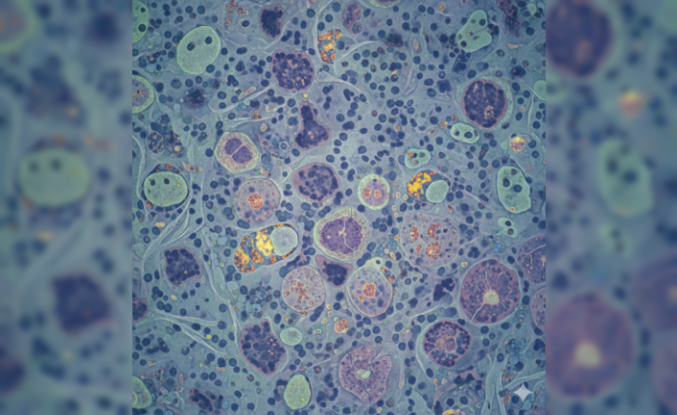

Bağışıklık Sistemi Kendi Kanına Karşı: Antifosfolipid Sendromu Tehlikesi

Vücudun savunma mekanizması bazen yönünü şaşırarak kendi sağlıklı hücrelerine saldırabiliyor. Tıp dünyasında Antifosfolipid Sendromu (APS) olarak bilinen bu durum, halk arasında daha çok "yapışkan kan" adıyla anılıyor. Kandaki proteinlere karşı gelişen hatalı antikorlar, damar tıkanıklıklarına ve hamilelik süreçlerinde ciddi risklere yol açmakta.